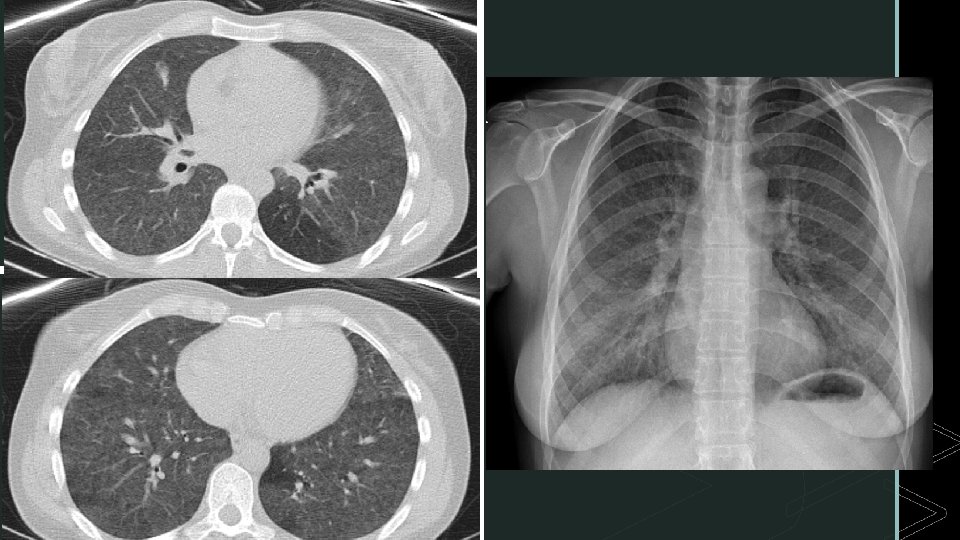

Pruebas complementarias: • Analítica: destaca: PCR 4, 84 mg/d. L [<0, 5], Linfocitos 9, 20% [37 -70%] • Gasometría arterial: normal: p. H 7, 40, p. CO 2 32, p. O 2 64, bicarbonato 24, sat. O 2 94%. • PCR en aspirado nasofaríngeo para Influenza y pruebas microbiológicas: negativo. PCR en LBA para neumocystis negativa. Quantiferon-TBC negativo. • PFR: DLCO muestra una disminución severa de la difusión. • Precipitinas alteradas para pájaros (Ig. G ESPECÍFICAS) • LBA linfocitosis y cociente CD 4/CD 8 invertido (<1). La Rx y el TACAR muestran la siguiente imagen

DIAGNÓSTICO: PATRÓN EN VIDRIO DESLUSTRADO GENERALIZADO BILATERAL ASOCIADO A NEUMONITIS POR z HIPERSENSIBILIDAD. TTO: evitar exposición a aves + prednisona VO con dosis en pauta descendente hasta mantenimiento de 30 mg/día. Seguimiento.